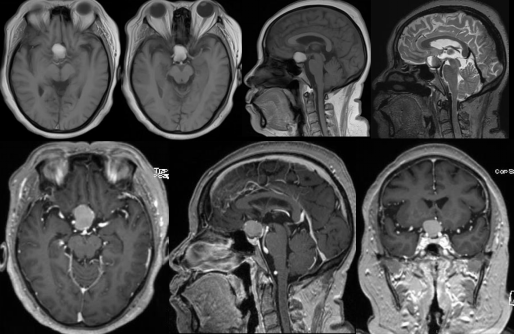

术前影像资料

肿瘤位于鞍窝及鞍上及前颅底处,肿瘤大小约4*5*5厘米,灰红色,边界尚清,肿瘤卒中,肿瘤质地较韧,血供丰富,肿瘤与垂体柄、双侧视神经、视交叉、双侧大脑前动脉、双侧颈内动脉粘连。